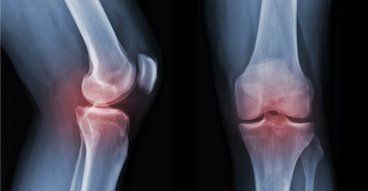

ما هو مرض هشاشة العظام؟

يعرف مرض هشاشة العظام باسم ترقق العظام أيضًا، فهو مرض يضعف العظم بمرور الوقت، حيث تنخفض فيه كثافة العظام، وتقل قوته، ويصبح أكثر عرضة للكسر.

تشخيص هشاشة العظام

ينصح الأطباء في حال كان لديك تاريخ عائلي للمرض، أو كان عمرك يزيد عن 50 عامًا، أو لديك أي عامل من عوامل الخطورة المذكورة أعلاه، بإجراء فحوصات كثافة العظام (DEXA) بانتظام

يستخدم فحص كثافة العظام مستويات منخفضة من الأشعة السينية لقياس كثافة عظامك وما تحتويه من معادن.

كما يعد فحص كثافة العظام من أفضل الفحوصات للكشف عن ترقق العظام في وقت مبكر قبل التعرض للكسر.